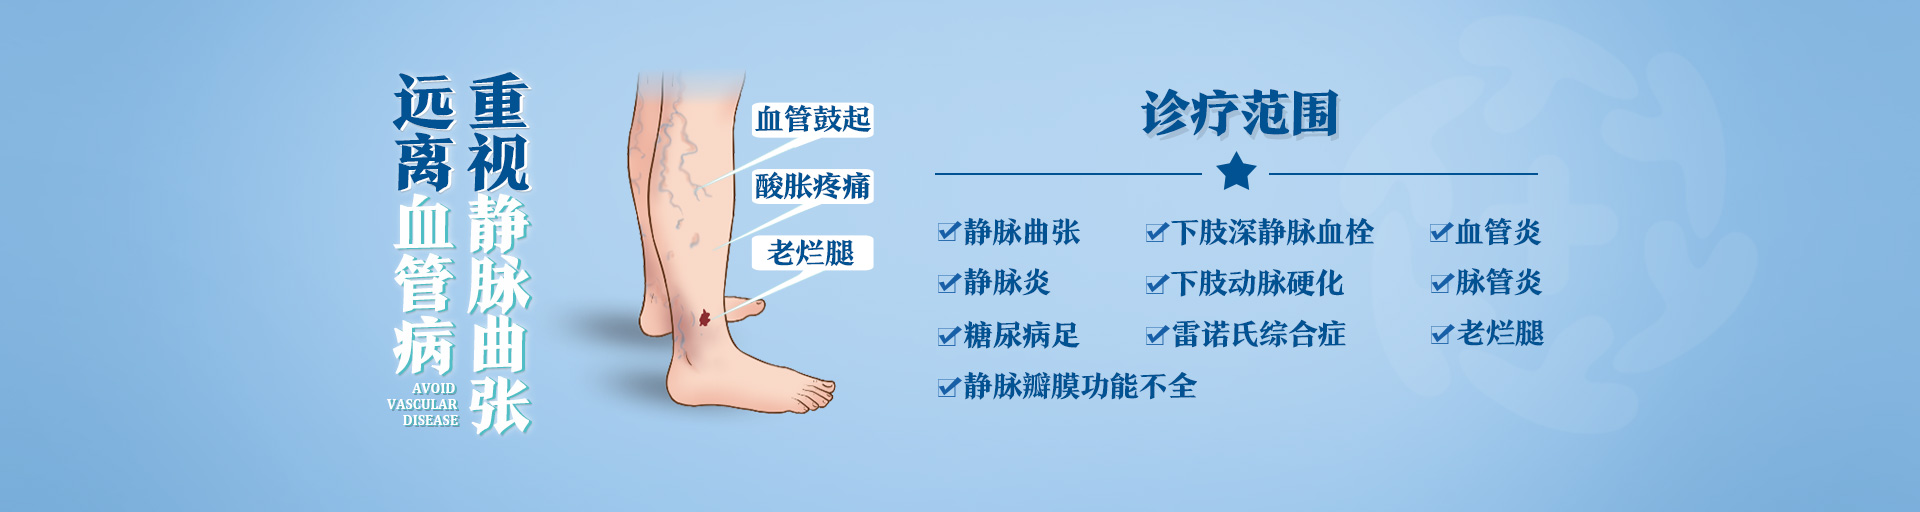

大隐静脉曲张拖延十余年丨30分钟,1根1mm光纤管子解决问题

大隐静脉曲张 14年前出现右腿肿胀加重4年 近日,陕西冶金医院血管外科成功为一位67岁大隐静脉曲张的患者施行大隐静脉曲张点式微创术+腔内激光术+静脉导入术,仅通过一个小创口和

糖尿病足丨忽视小病,现在后悔不已...

我是一名医生 一辈子救死扶伤 可是,人都会生病 我也不会例外 病来如山倒,一点也不假 可是,这个糖尿病足不是我的擅长 疼,还是疼 脚疼彻心扉 疼的想拿起手术刀把脚给剁掉 疼的